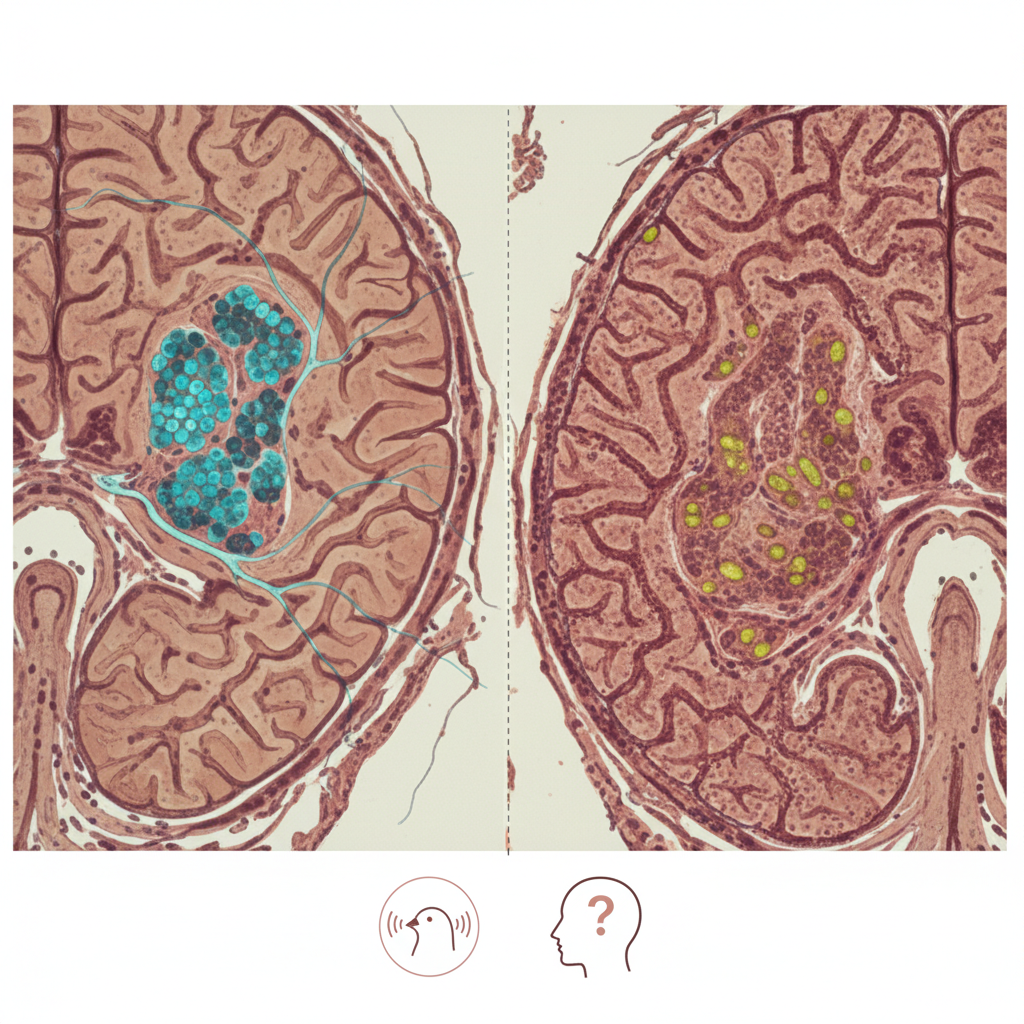

A manchete pode soar ampla, mas a melhor leitura editorial é muito mais específica. Esta não é uma história sobre um tratamento universalmente superior para todo câncer de pulmão avançado. É uma história sobre oncologia de precisão.

Isso significa que o benefício depende de uma pergunta central: o tumor tem uma alteração molecular acionável?

Se a resposta for sim, a terapia-alvo pode transformar o início do tratamento. Se a resposta for não, esse mesmo medicamento provavelmente não terá o mesmo impacto — e outras estratégias, como imunoterapia, quimioterapia ou combinações, podem ser mais apropriadas.